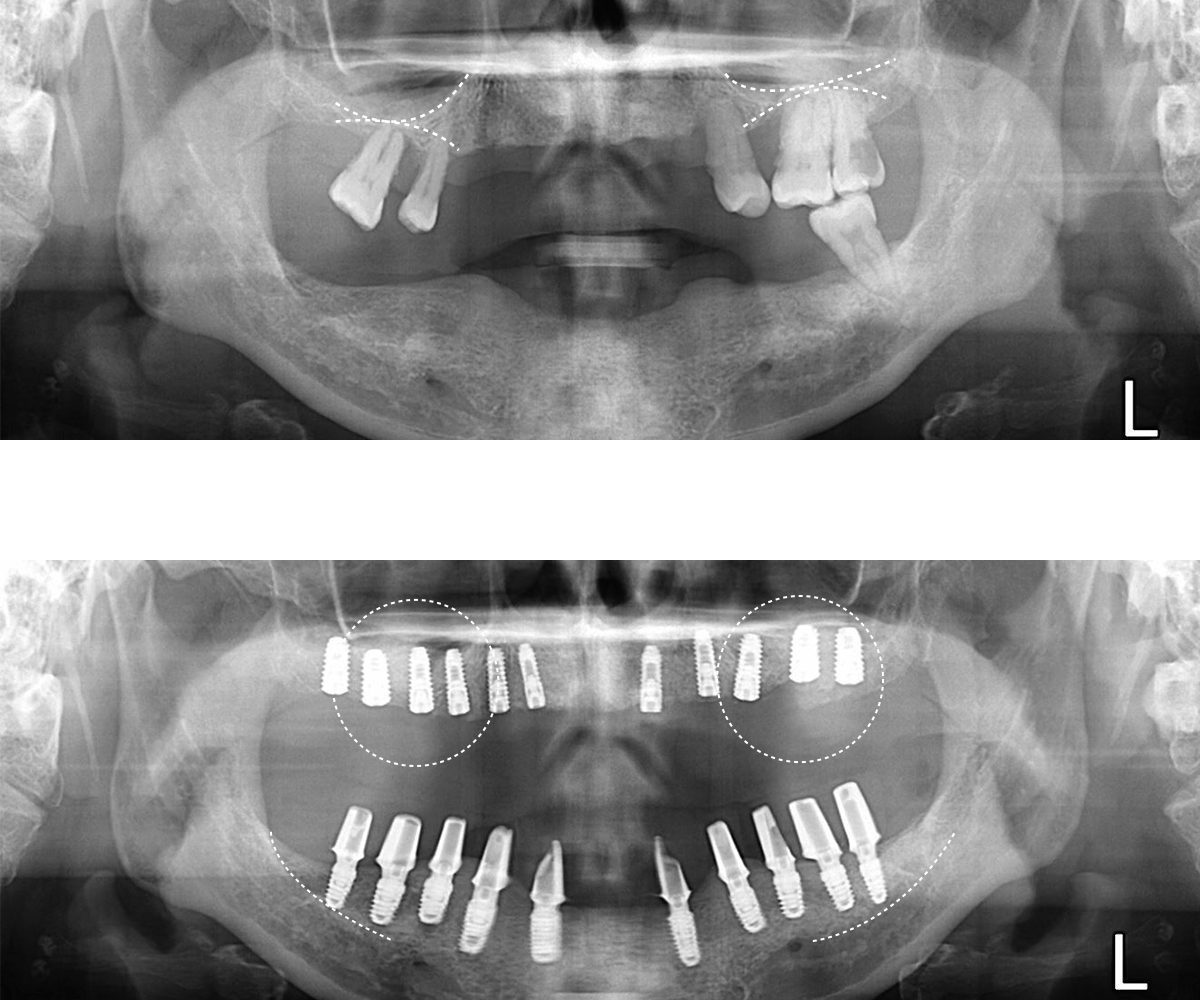

전악임플란트

60대 여성 환자분 사례입니다.

요즘 시대에 비교적 젊은 나이 시지만 오랜 기간 동안 틀니 사용으로 잇몸뼈가 녹아 위턱뼈는 1mm 정도 남아있고 아래턱뼈는 신경관과 많이 근접한 상태입니다.

일반적으로 위아래 전체 임플란트는 각각 8개의 임플란트로도 가능하지만, 지금은 뼈가 충분하지 않아 작은 임플란트로 일반적인 개수보다 추가적으로 더 식립하여 시술했습니다.

위턱은 상악동 거상술, 아래는 골이식과 수평골 증강술(ridge expansion)을 시행하여 뼈의 볼륨을 증가시키면서 동시에 임플란트를 식립했습니다.